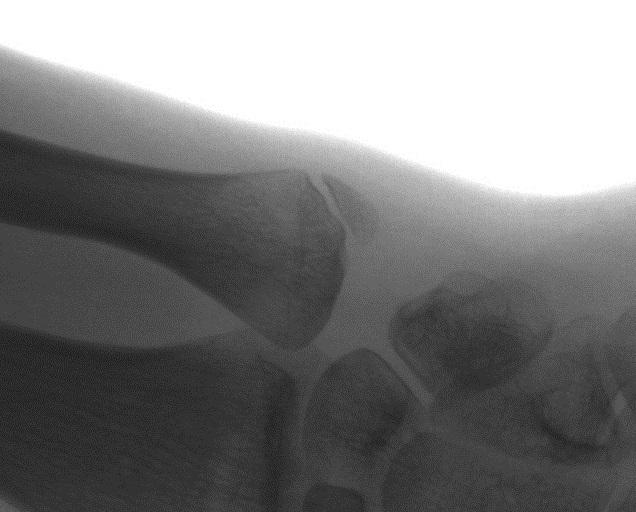

Врачом-рентгенологом клиники Витерра получены рентгеновские снимки обеих кистей, где выявлен перелом шиловидного отростка локтевой кости с признаками формирования отдельной кости из отломка без срастания места перелома.